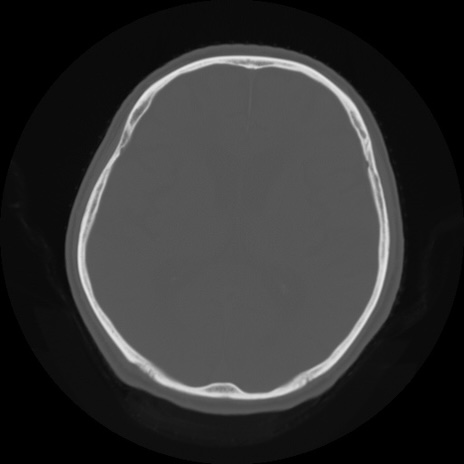

【頭部】症例5 CT(横断像)

【症例】80歳代 男性

【主訴】頭部打撲

【現病歴】外出先で椅子から立ち上がる際に、つまづいて後方へ転倒し受傷。転倒時に意識はあった。

【身体所見】BP 217/71、HR 96、JCS1-1、 難聴あり、顔色良好、右後頭部に擦過創あり。神経学的異常なし。

症例5の画像所見と診断は?